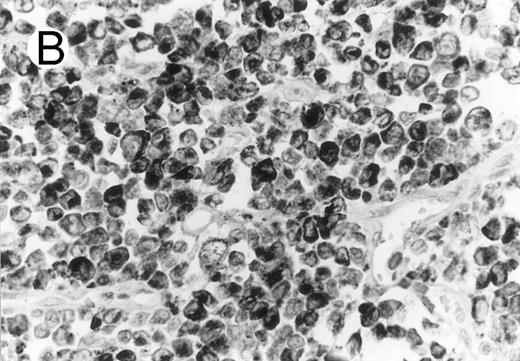

Anaplastic large cell lymphomas of T-cell and ‘null’-cell type.The results are summarized in Tables 1 and 2. Twenty-three (70%) of the 33 ALCL cases revealed TIA-1 positivity in the lymphoma cells. In 20 of the 23 positive cases virtually all tumor cells were positive, while in the remaining 3 cases less than half of the tumor cells showed TIA-1 positivity. Sixteen TIA-1+ cases displayed a T-cell phenotype, six revealed a null-cell phenotype, and one had an ambiguous phenotype staining with both T-cell and NK-cell markers. Positive staining was seen in 13 out of 19 (68%) CS forms, and all (100%) of the 6 HR and 2 SCP variants. The typical staining pattern was granular and cytoplasmic, with frequent paranuclear staining in the Golgi region (Fig 1). The 2 SCP cases showed homogenous granular TIA-1 reaction in both the small cell and the CD30+ large cell components. In addition, 2 of the 3 AIDS-associated cases (67%) showed positive staining, whereas none of the 3 PC forms marked for TIA-1. Beside neoplastic cell staining, small reactive lymphocytes with a similar typical granular staining pattern were seen in all cases investigated. These lymphocytes represented scattered interfollicular and intrafollicular small cells, but in some cases accounted for up to 40% of the non-neoplastic paracortical lymphocytes either in the involved or uninvolved lymph node regions. Cytoplasmic TIA-1 staining also occurred in normal granulocytes, but with a less distinct granular pattern than in positive lymphocytes. In some cases, occasional epithelioid histiocytes displayed weak, diffuse cytoplasmic staining. TIA-1+ tumor cells revealed a distinct granular staining pattern that was always easily distinguishable from reactions of granulocytes and epithelioid histiocytes.

Cytotoxic granule antigen expression in a common form of ALCL (Table 2; case 11). (A) Immunostain for CD30 highlights sheets of large tumor cells. (B) The tumor cells of this case display granular cytoplasmic TIA-1 immunoreaction with paranuclear accumulation in the Golgi region. (C) Strong cytoplasmic perforin reaction is shown in the same case. (sABC-peroxidase technique, hematoxylin counterstain, original magnification × 400.)

Twenty-two ALCLs (67%) showed perforin+ neoplastic cells. Three of them were focally positive showing perforin staining in less than half of the large atypical cells. The perforin+ cases comprised 14 of 19 CS forms (74%), 6 of 6 HR (100%), and 2 of 2 SCP variant cases (100%). Perforin+ tumor cells were not detected in any of the AIDS-associated and PC cases. The perforin+ neoplastic cells showed either a dot-like paranuclear or a diffuse cytoplasmic reaction, with frequent perinuclear accumulation outlining the nuclear membrane (Fig 1). Occasionally granular staining was also present in some tumor cells. In the SCP variants, both CD30− small atypical cells and CD30+ large lymphoma cells showed perforin positivity, although the large cells displayed a more intense homogeneous reaction. Scattered non-neoplastic, perforin+ small lymphocytes, displaying a granular reaction were detected in nearly every case in uninvolved sinuses and in the paracortex, providing a convenient endogenous positive control of the immunoreaction. The perforin+ lymphocytes were generally present in much smaller numbers than TIA-1 positive reactive lymphocytes.